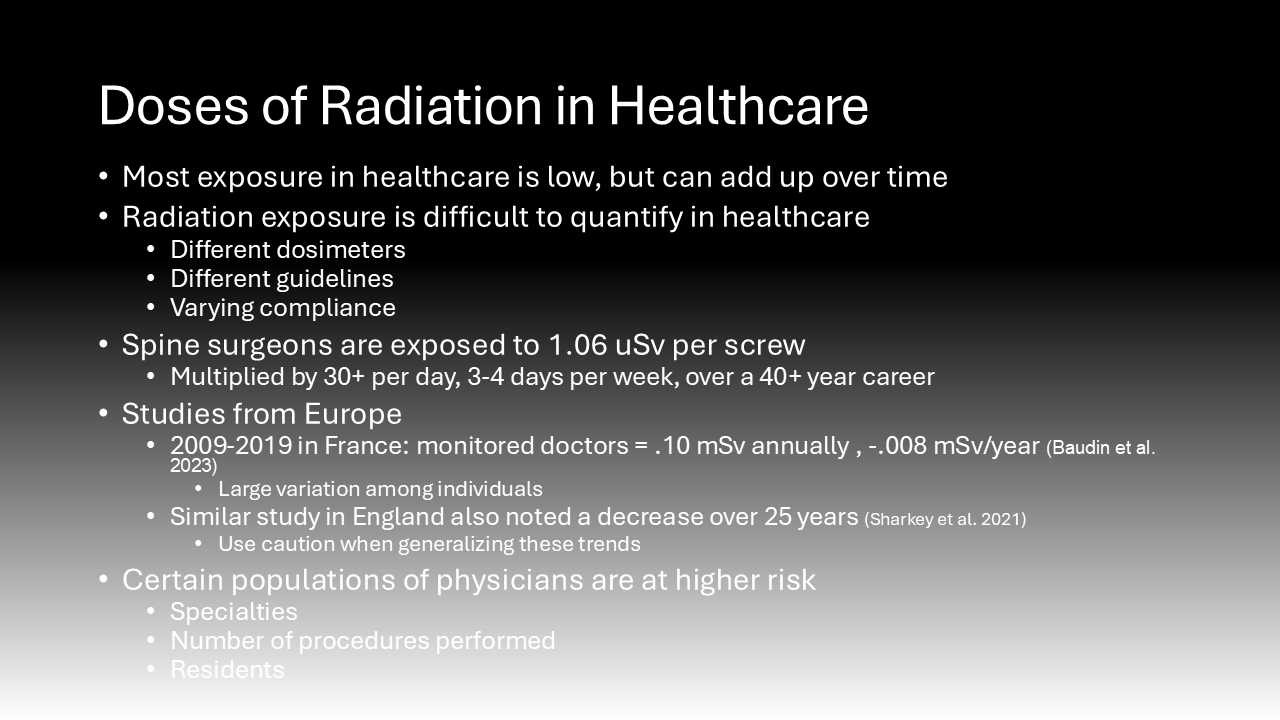

The effects of radiation are dose-dependent.6 This means that while the potential damage from the low doses of radiation used during a medical procedure is slight, it is the cumulative effects of this chronic exposure in healthcare workers that are worrisome.6 It is logistically challenging to track radiation exposure in the healthcare setting because there are different types of dosimeters and various sets of guidelines for their use that differ by institution.7 Additionally, though they are mandated to wear dosimeters, individuals vary in their compliance with safety practices and protective shield use, which will be discussed later.7 While data on US physicians is lacking, several retrospective cohort studies in Europe have determined levels and trends of radiation exposure in healthcare workers.7 The standard unit for radiation is a gray (1 joule of energy absorbed by 1 kilogram) but when considering the harmful effects of radiation, grays are multiplied by a quality factor to convert to Sieverts (Sv).4

The use of fluoroscopy mainly exposes surgeons to scatter radiation, which is a lower dose as opposed to direct radiation that patients experience.8 However, this scatter radiation exposure in physicians accumulates significantly over time. Prior investigation demonstrates that spine surgeons using fluoroscopy are exposed to an average of 1.06 uSv per screw.8 Spine surgeons may place as many 30+ screws per day, 3-4 days per week, multiplied over a 40-year career.8 To put this in perspective, studies of survivors of the Hiroshima bombing have shown that being exposed to just one Sv is associated with a 60% increased chance of developing a solid malignancy.8 While the use of fluoroscopy is critical for patient safety and surgical success, the exposure experienced by physicians accumulates significantly over time.8

Few studies abroad have attempted to quantify trends in occupational exposure to radiation among physicians over time. One study of three hospitals in France determined that monitored healthcare workers were exposed to .10 mSv annually, averaged from 2009 to 2019, with a -.008 mSv/year trend. This translates to a 58% decrease over that 10-year period.5 However, there was considerable variation between individuals, with some experiencing 0 Sv while others experienced several tenths of a Sv each year.5 Another study conducted in England over 25 years determined that the radiation dose experienced by doctors in their cohort similarly decreased.9 While this data seems promising in that it demonstrated a reduced radiation dose experienced by physicians despite increased use of the technology, the authors of both studies warn of false reassurance.9 They state that these results may not be widely applicable due to increased monitoring and regulation of European working hours.9 Additionally, they attribute much of the decrease in exposure observed to an increase in the number of dosimeters reporting zero dose, which could be due to the dose falling below the detection limit of .05 mSv.5 This means that while lower doses of radiation may be used and are below the detection capabilities, we are unsure how their cumulative effect could add up.5 The authors warn that despite this measured trend, the risks of exposure to ionizing radiation in the healthcare field are still significant.9

It is important to note that these studies on the average dose of radiation experienced by physicians annually do not account for the heterogeneity that leads to some physicians being exposed to much higher doses than average.7 For instance, based on the duration of training and the number of procedures performed, one study concluded that neurosurgeons experience greater radiation doses than doctors in other specialty programs that use intraoperative imaging.7 Additionally, another study found that comparatively few anesthesiologists were issued dosemeters compared to surgeons when they, too, were exposed to radiation.9 The literature also likely underestimates the dose of radiation experienced by physicians in residency training for several reasons.9 Residents may wear lead protection less frequently due to the lax attitudes of some supervising staff who trained when radiation safety was less emphasized.7 These physicians-in-training are less likely to have properly fitting lead protection due to the costs associated with its purchase.10 Finally, residents often overuse intraoperative imaging compared to attending physicians performing the same procedure due to their inexperience and higher dependence on checking their work with images.7 The combination of these confounding factors necessitates caution when generalizing the results of studies demonstrating that radiation doses are down-trending.7 Additionally, although increased dose leads to increased risk, it is essential to remember that no level of radiation exposure is considered “safe.7”